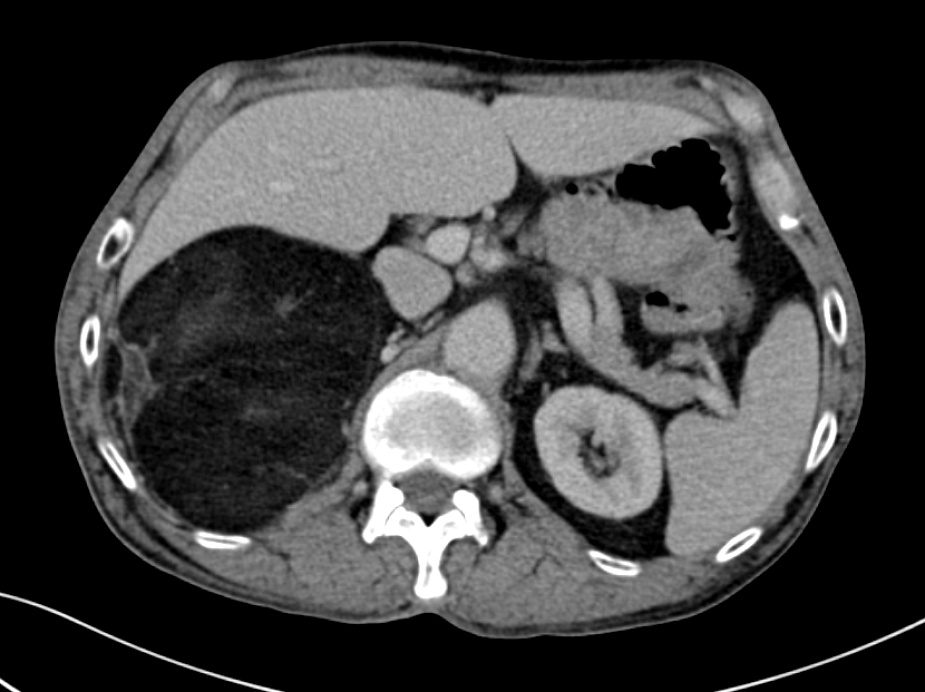

腹部CT:右肾上腺巨大肿瘤

年过六旬的彭老重度哮喘已有10余年,还患有重度慢性阻塞性肺病。然而,彭老还是一位“老烟枪”,就这样一边哮喘住院,一边抽着烟,谁也劝不动。五年前,老先生被发现长了一个肾上腺良性肿瘤,当时大约有鸡蛋大小,谁知,如今竟然长到了将近20cm,像个小篮球。

蔡志康联合呼吸科、麻醉科制定了缜密的手术方案,对每一步潜在的风险都做好了预案。手术当天,在打开彭老的腹腔后,只见硕大的肿瘤几乎霸占了右侧腹腔一半的空间。在分离肾脏时,发现肿瘤包膜与肾包膜粘连严重,在评估肾脏完好后,用超声刀将界限一点点游离开来。就这样一点点地攻克每一个难点,肿瘤终于被完整地切除了下来。经测量,肿瘤的最大径达到了20cm。